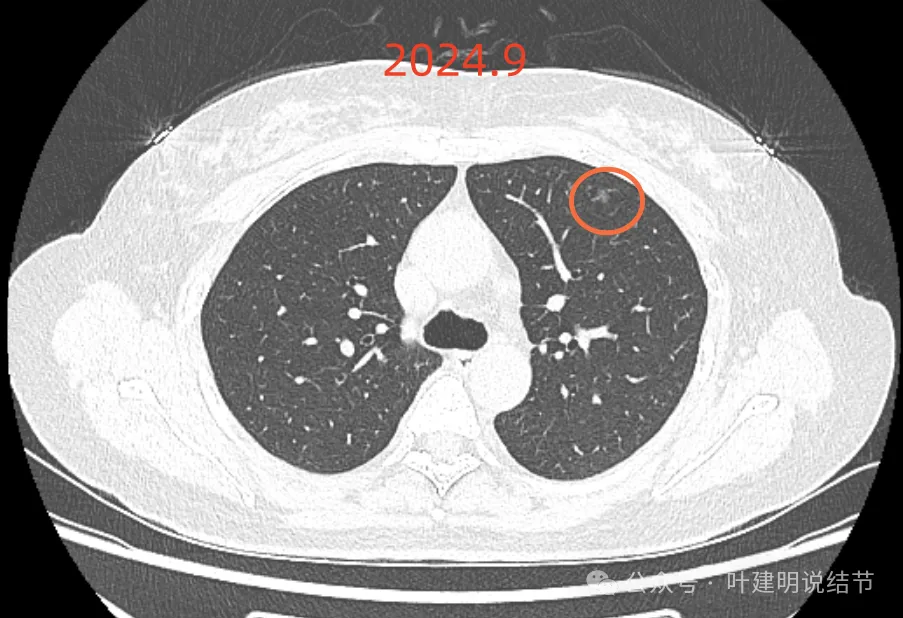

7、2024年9月,时隔1年再在A医院复查薄层CT,呼吸内科医生发现右上肺的主病灶比2022.2月缩小了。

影像展示与分析:

我们先来看2022年2月时病灶最明显部位的截图:

这是A医院主张手术时的影像:

最后来看2024年9月,也就是叫停手术后2整年之后复查的情况:

仍说不上有明显进展,如果将这几次的放在一起来对照,就会更加直观:

病灶基本上没有明显变化。当然不必过于在意具体大小有没有几毫米的差别,也不必在意具体CT值有几十或百把的区别,微细的差别不影响临床决策,也就是说改变都不足以让肉眼发现的,怎么会影响预后呢!

我看了你2022年2月时的片子,以及某医院建议你手术说有进展时的2022年5月时的片子和2023年8月复查时的片子,再对比2024年9月时的影像,总体上明显点的病灶仍是这三处。首先均仍是纯磨,有的似有微血管进入或穿行,但磨玻璃成分密度很淡,而且大小无明显进展。至于右上病灶是否有缩小好转,感觉上右上的与右中叶的都略显淡了点,我怀疑还是扫描条件不一的关系,本身又是非常小而淡的病灶,可比性稍差,并不能说明必是有吸收好转。但肯定说不上有进展,风险仍是低的,半年或一年复查随访(个人倾向可以年度复查)总归不至于会耽误病情。意见供参考!